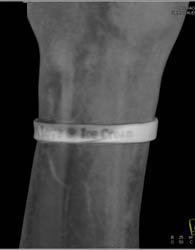

Cellulitis